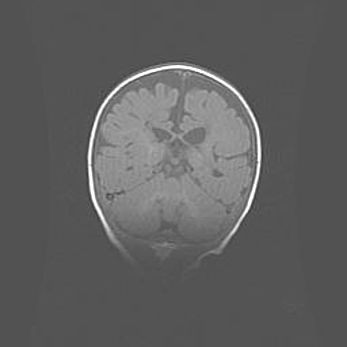

Сообщающаяся гидроцефалия. Кистозная энцефаломаляция головного мозга.

Возраст: 3 месяца 4 дня

Вес: 3100 г

Пол: женский

Окружность головы: 34 см

Срок гестации: 31 неделя

Кистозная энцефаломаляция головного мозга - одна из форм поражения головного мозга в детском возрасте. Характеризуется возникновением множественных и распространённых кист в коре, белом веществе и подкорковых образованиях головного мозга у плодов, новорождённых и детей раннего возраста. Развитие кистозной энцефаломаляции связано с внутриутробной асфиксией и гипотонией, родовой травмой, тромбозом синусов, пороками развития сосудов, инфекциями, сепсисом и другими причинами. Наиболее значимые инфекционные агенты: вирусы простого герпеса, цитомегалии, краснухи, токсоплазмы, энтеробактерии, золотистый стафилококк и другие.